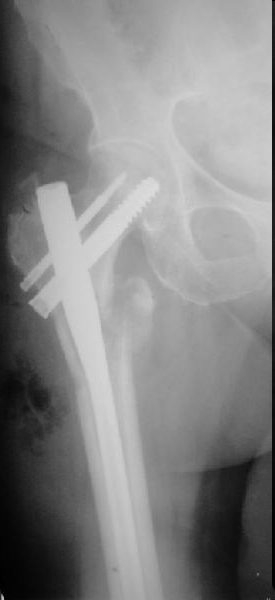

Это типичная проблема, вот аналогичный случай. Удалили, исправили,

фиксировали другим PFN.